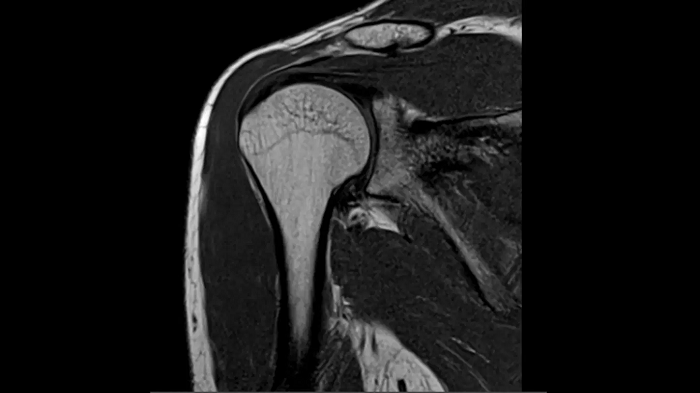

Shoulder

PD TSE Fat Sat with Deep Resolve and Simultaneous Multi-Slice

Exceptional fat suppression and performance for the shoulder’s clear imaging. Integrating the Deep Resolve’s power with the proven Simultaneous Multi-Slice technique.

SMS 2 | Deep Resolve Gain & Sharp

0.4 x 0.4 x 3.0 mm2

TA 3:20 minutes

MAC-ID: 7aaaa0213. Image Credit: Siemens Healthineers

T1 TSE with Deep Resolve and Simultaneous Multi-Slice

Outstanding T1 imaging of the shoulder using MAGNETOM Free.Star. Integrating the Deep Resolve’s power with the proven Simultaneous Multi-Slice technique.

TA 3:37 minutes